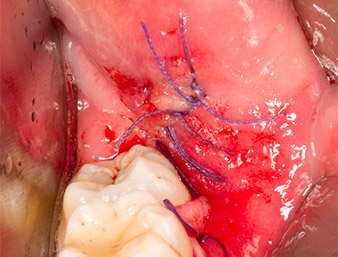

Nachfolgend wurde das autogene Knochengewebe (Abb. 13) in die Alveole und den umliegenden Knochendefekt eingebracht (Abb. 14). Kollagenvlies bedeckte als Schutz für den freiliegenden Nerv die Knochenspäne bis auf Knochenniveau (Abb. 15).

Knopfnähte mit Vicryl-Fäden der Stärke 4.0 verschlossen das aufgeklappte Weichgewebe (Abb.16). Postoperativ wurden ein Ibuprofen-Präparat (Seractil 400 mg, 3x1) und ein Antibiotikum aus Amoxicillin und Clavulansäure (Augmentin 1 g, 2x1) verschrieben.